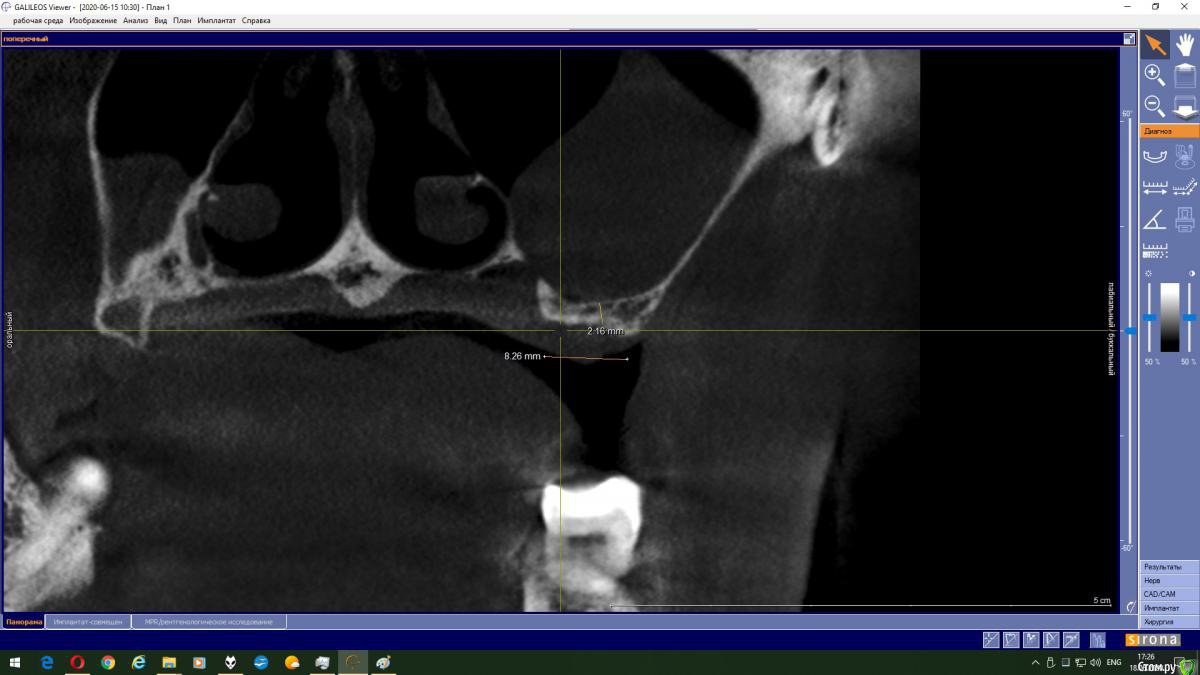

Magnoliya Опубликовано 18 июня, 2020 Поделиться Опубликовано 18 июня, 2020 Здравствуйте, прошу Вашей помощи и консультации. Все доктора, у которых я уже побывала говорят противоположные вещи, сложно принять решение. Очень надеюсь, что вы сможете посмотреть КТ, и выскажете своё мнение. http://fayloobmennik.cloud/7398744 Предыстория удалила 6 и 7 на левой верхней челюсти в надежде, что через 4 месяца сделаю открытый синус-лифтинг с подсадкой костной ткани и затем установлю импланты,но когда принесла КТ врачу перед операцией, он сказал, что синус лифтинг противопоказан, так как в гайморовой пазухе киста, и костной ткани мало, от слова ОЧЕНЬ МАЛО. В его видении решении моей проблемы был скуловой имплант Zigoma. при котором сразу после операции я выйду с зубами, естественно с другой суммой на операцию, на которую я не расчитывала. Тут я решила пойти на консультацию к другим специалистам, чтоб принять решение. На сегодняшний день есть 3 варианта, которые озвучили мне доктора: 1. Операция со скуловым имплантом с одномоментной установкой коронок2. Обратиться к ЛОРу и удалить кисту, затем синус лифтинг и т.д.3. Один врач сказал мне, что киста не мешает и можно делать синус лифтинг не удаляя кисту??? Действительно ли так? Можно ли избежать операции по удалению кисты? Заранее спасибо всем тем, кто хоть как то поможет советом Ссылка на комментарий

колесников Опубликовано 18 июня, 2020 Поделиться Опубликовано 18 июня, 2020 Глупости какие! Для чего зигомы? Доктора видимо смутил рельеф дна пазухи,там много перегородок,выступов,что затрудняет отслаивание мембраны. Можно провести имплантацию одновременно с синуслмфтингом,а кисту и вовсе не трогать. 1 Ссылка на комментарий

Bier Опубликовано 18 июня, 2020 Поделиться Опубликовано 18 июня, 2020 Данную кисту убирать не нужно. Нет показаний для зигомы. Делайте синуслифтинг и имплантат. Ссылка на комментарий

колесников Опубликовано 19 июня, 2020 Поделиться Опубликовано 19 июня, 2020 Выходить можно сделать синус лифтинг не трогая кисту. В дальнейшем ничем это не грозит? Я имею ввиду киста не вытечет на импланты? И может ли киста со временем рассосаться сама? это не инфекционного происхождения киста,слизистая железка закупорилась,может надуваться,может лопнуть самостоятельно,у вас она на боковой стенке пазухи,синуслмфтингу не помеха Ссылка на комментарий